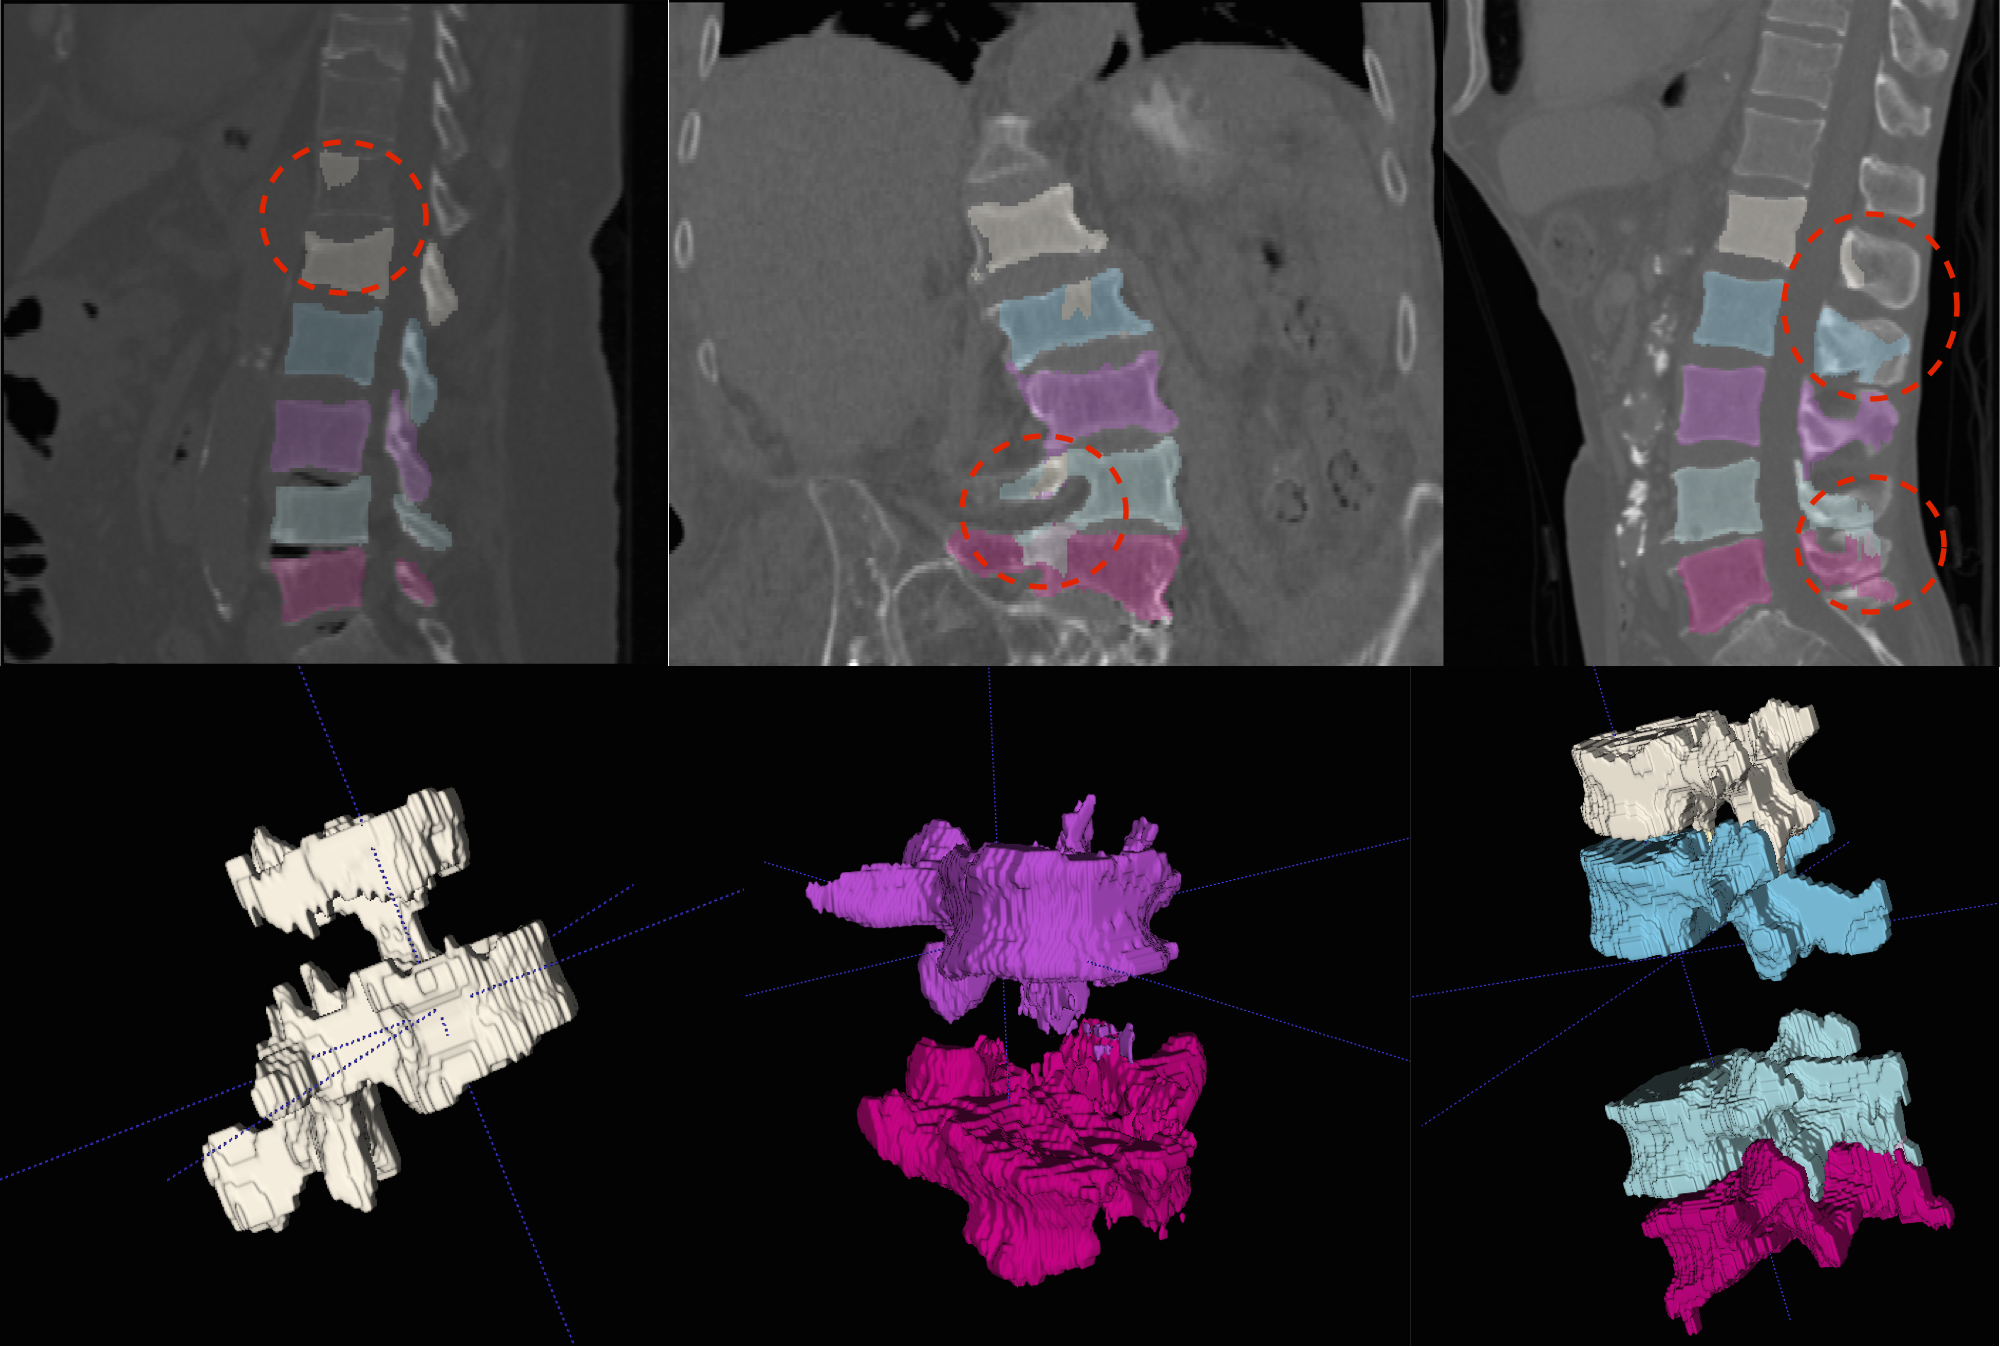

We present more results of multi-class segmentation on the test set of xVertSeg (figure 5) in addition to the results in figure 4, thereby emphasising the robustness of our approach. We also present a few aberrant segmentations analysing which could further improve our approach.